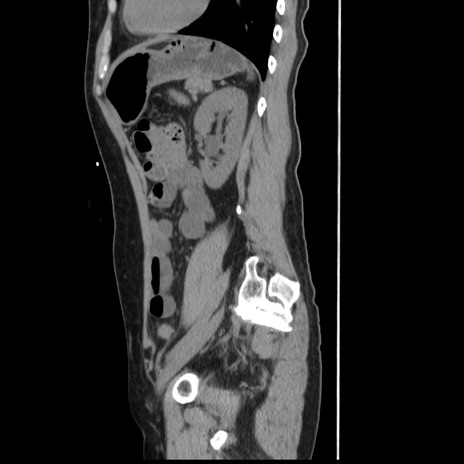

症例10(矢状断像)

【症例】 50歳代女性

【主訴】 腹痛

【現病歴】前日生レバーを食べた。今朝に排便あり。 昼前に突然発症の腹痛を生じ、当院救急外来を受診した。

【既往歴】 子宮筋腫にてで子宮全摘後

【身体所見】 意識清明、腹部:平坦、軟、下腹部やや左を中心に圧痛・反跳痛あり、筋性防御あり

【データ】WBC 7800、CRP 0.07